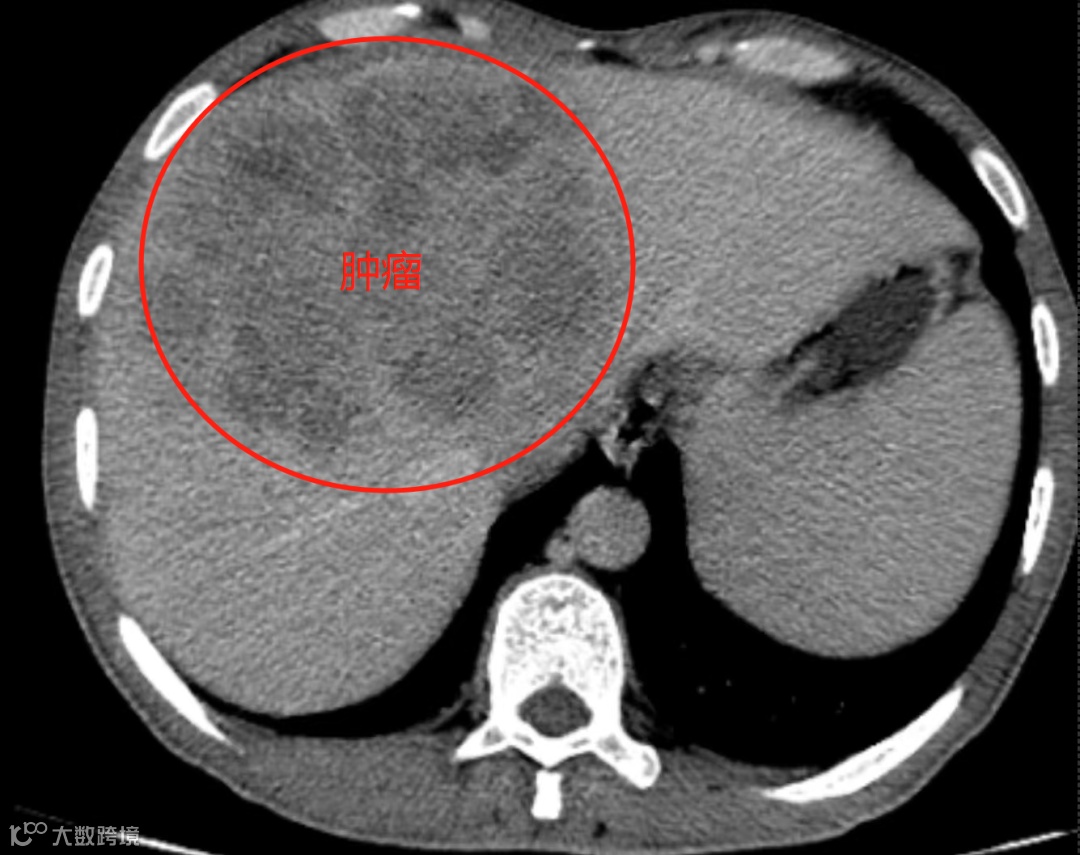

巨大肝恶性肿瘤

手术切除是实现肝癌根治和长期生存的重要手段。但元叔肝脏肿瘤体积过大,约16cm*11cm。

而且这个肿瘤的位置很刁钻,紧贴第二肝门,紧贴下腔静脉、肝右静脉,肝中静脉穿入肿瘤瘤体后消失不见,根部影像无法显示。比拇指还粗的肝后下腔静脉不仅被肿瘤包裹住,还直接被“霸道”的肿瘤给挤扁了,不排除被肿瘤侵犯可能。肿瘤的顶部还和膈肌紧贴着,有被侵犯可能。直接手术难度大,预后也不好。降期治疗是较好选择。